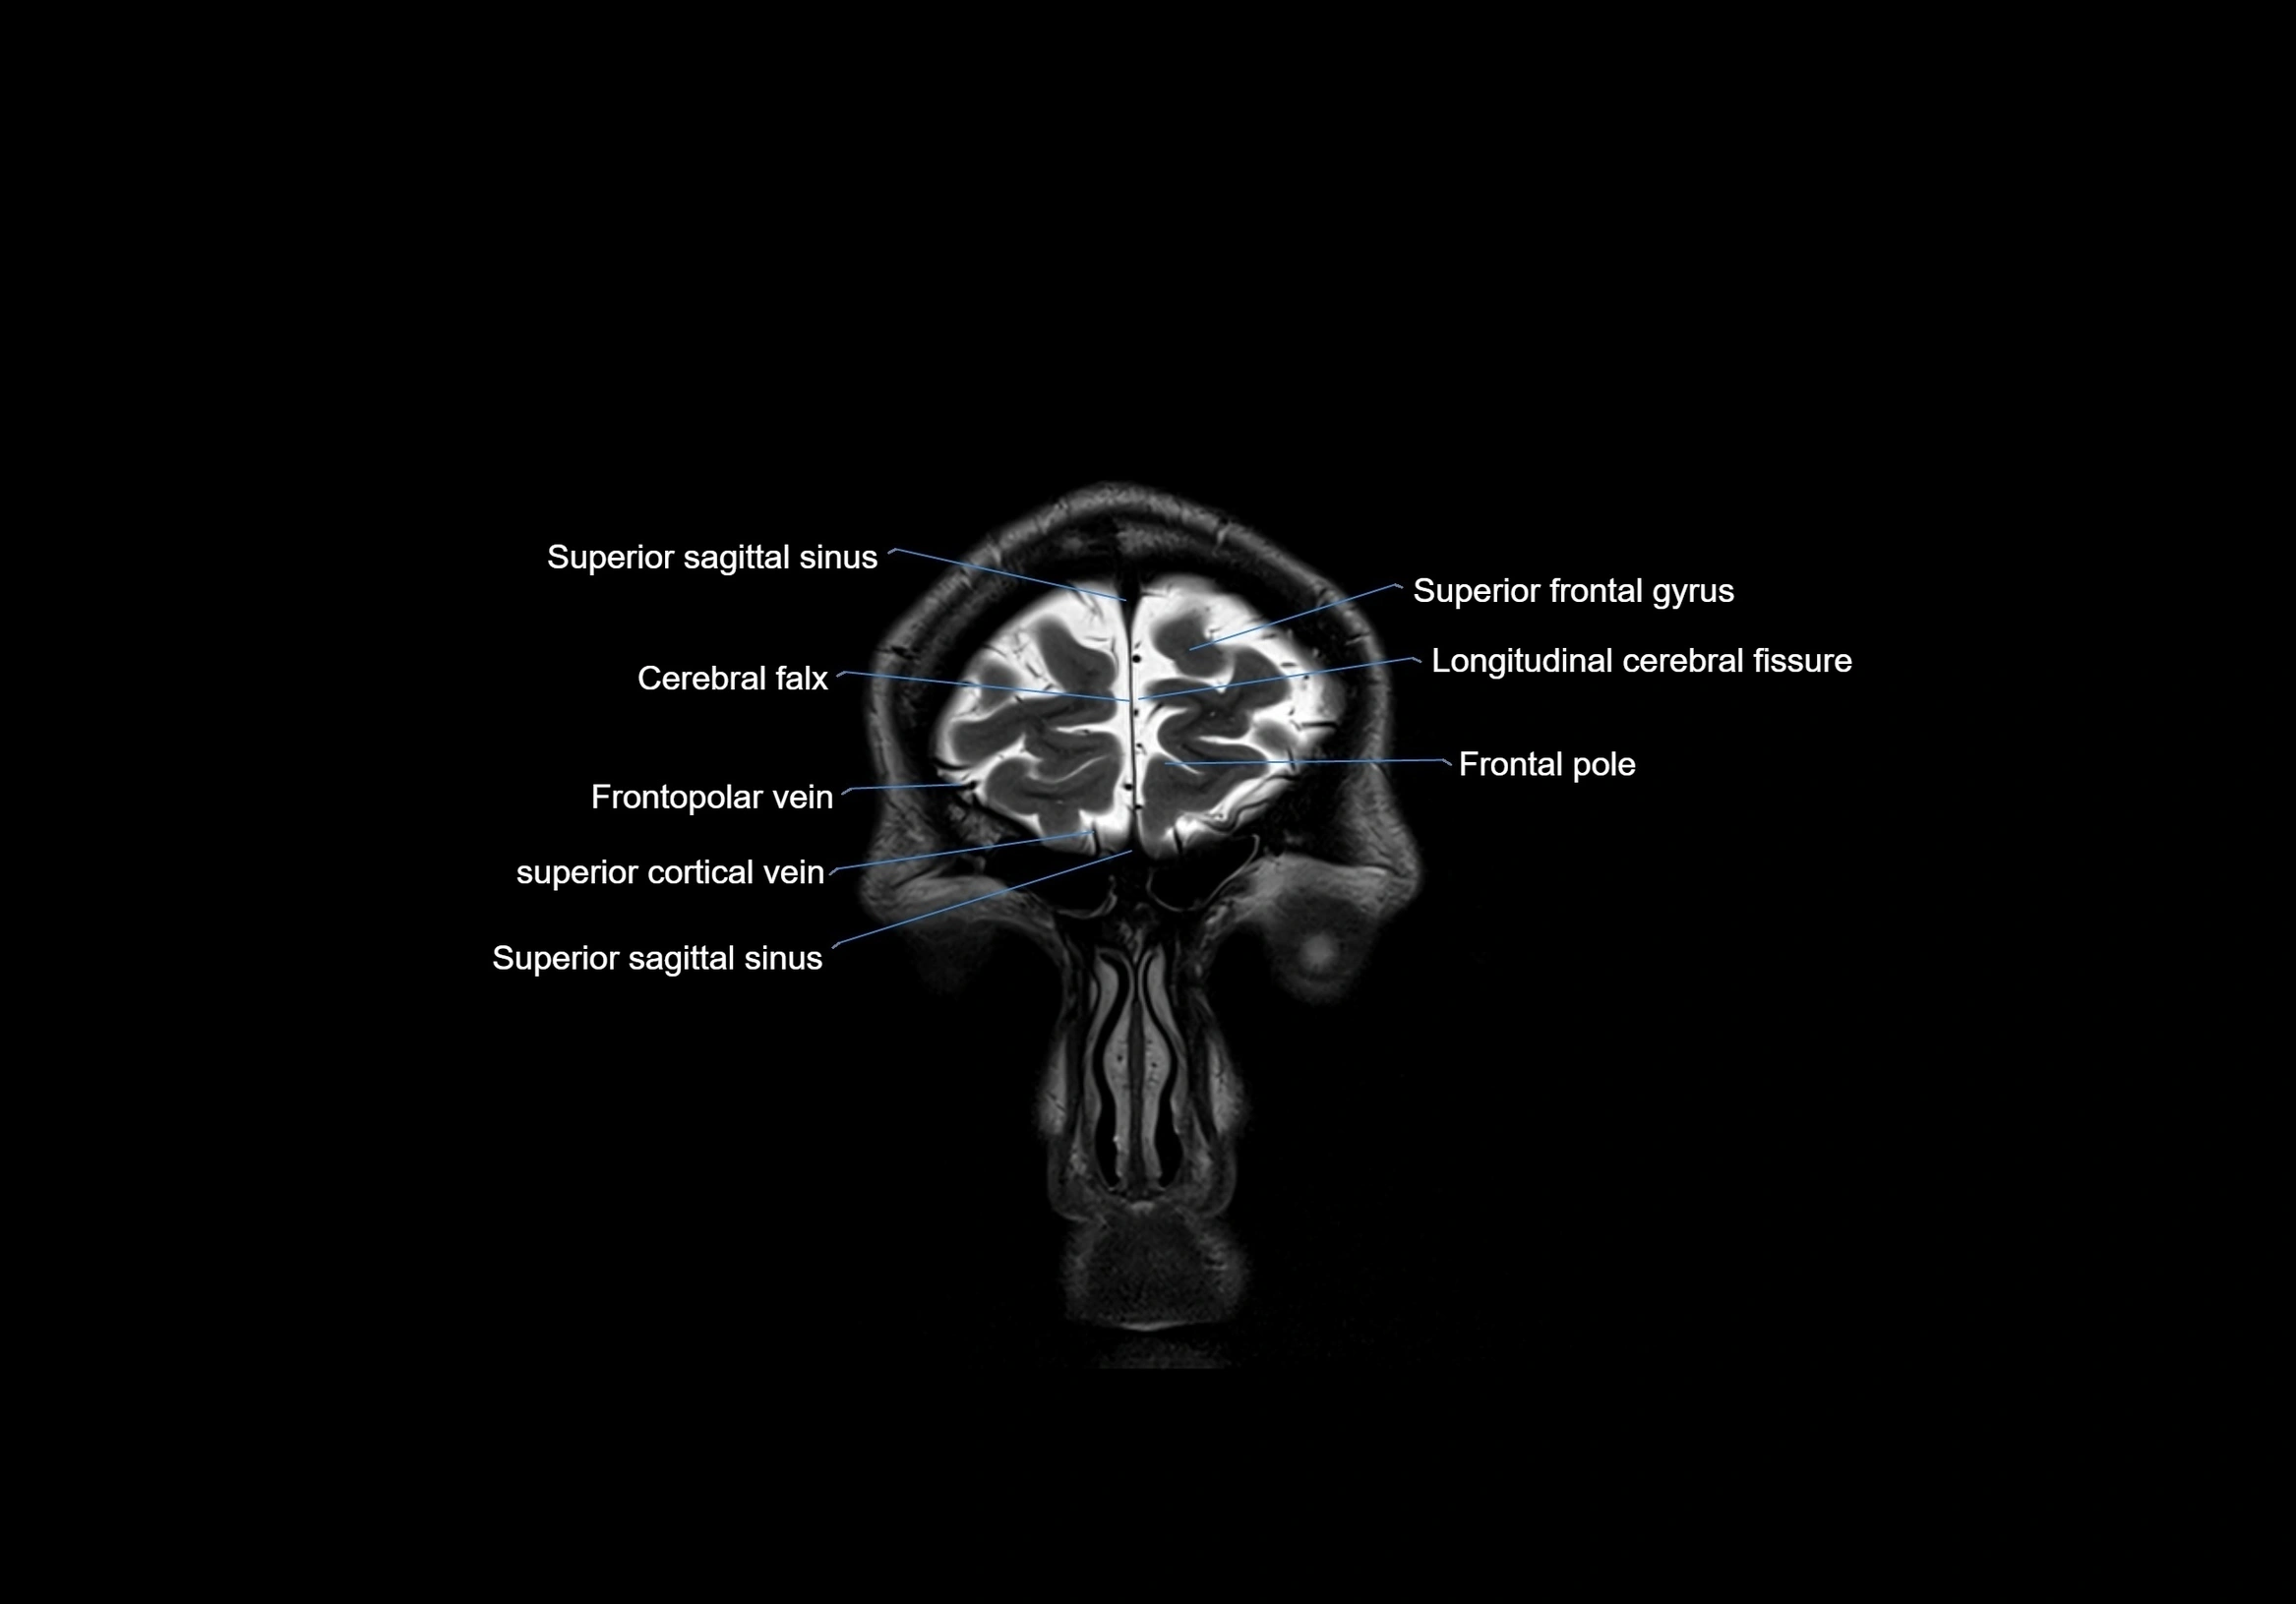

MRI images